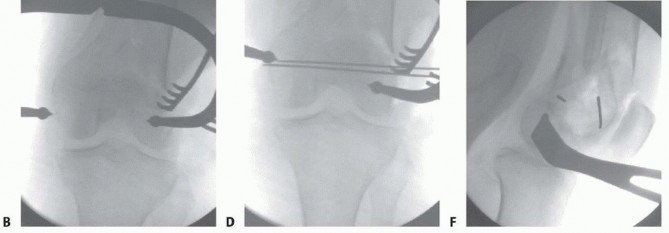

### TECH FIG 12 • A. Visualization of the joint for articular reduction. B. C-arm image of reduction forceps holding the intercondylar split reduced. C,D. Clinical photographs with forceps followed by guidewires for screw placement. E,F. Lateral views showing pins and wires outside the zone for either plate application or intramedullary nail. The anterior and posterior placement of the pins is seen. (continued) A reduction forceps is placed anteriorly to hold the reduction ( TECH FIG 12B). Temporary Kirschner wires or guidewires from a cannulated system can be placed for additional stability ( TECH FIG 12C,D). All clamps, Kirschner wires, or guidewires should be placed outside the zone of plate application ( TECH FIG 12E,F). 488

TECH FIG 11 • Patient with closed distal femur fracture (also shown in FIG 5G,H and 6C-E). A. Limited lateral incision, with the tibial tubercle marked. B. Skin incision showing the iliotibial band. C. Incision of the iliotibial band. D. Exposure of the lateral aspect of the femur. 487 ### Stabilizing the Articular Surface For nondisplaced type C1 or C2 fractures, the first priority is to stabilize the articular surface. Visualization of the joint may be accomplished with placement of a blunt Hohmann retractor (or similar Z retractor) ( TECH FIG 12A).

--- - TECH FIG 12 • (continued) G. Definitive fixation of the condyles with 4.5-mm partially threaded cannulated screws. Definitive fixation of the condyles should be performed (see technique description earlier) ( TECH FIG 12G). ### Reduction of the Distal Segment and Plate Placement Reduction of the distal segment to the shaft can be performed using temporary Steinmann pins ( TECH FIG 13). The plate can now be applied in a submuscular fashion (see Placement of the Plate section earlier). ### Wound Closure Final radiographs are taken in the operating room ( TECH FIG 14). Standard wound closure is undertaken, as described in the previous section. ### Retrograde Nailing(FIG 10A-F) Refer to Chapter 43 on retrograde nailing of the femur.